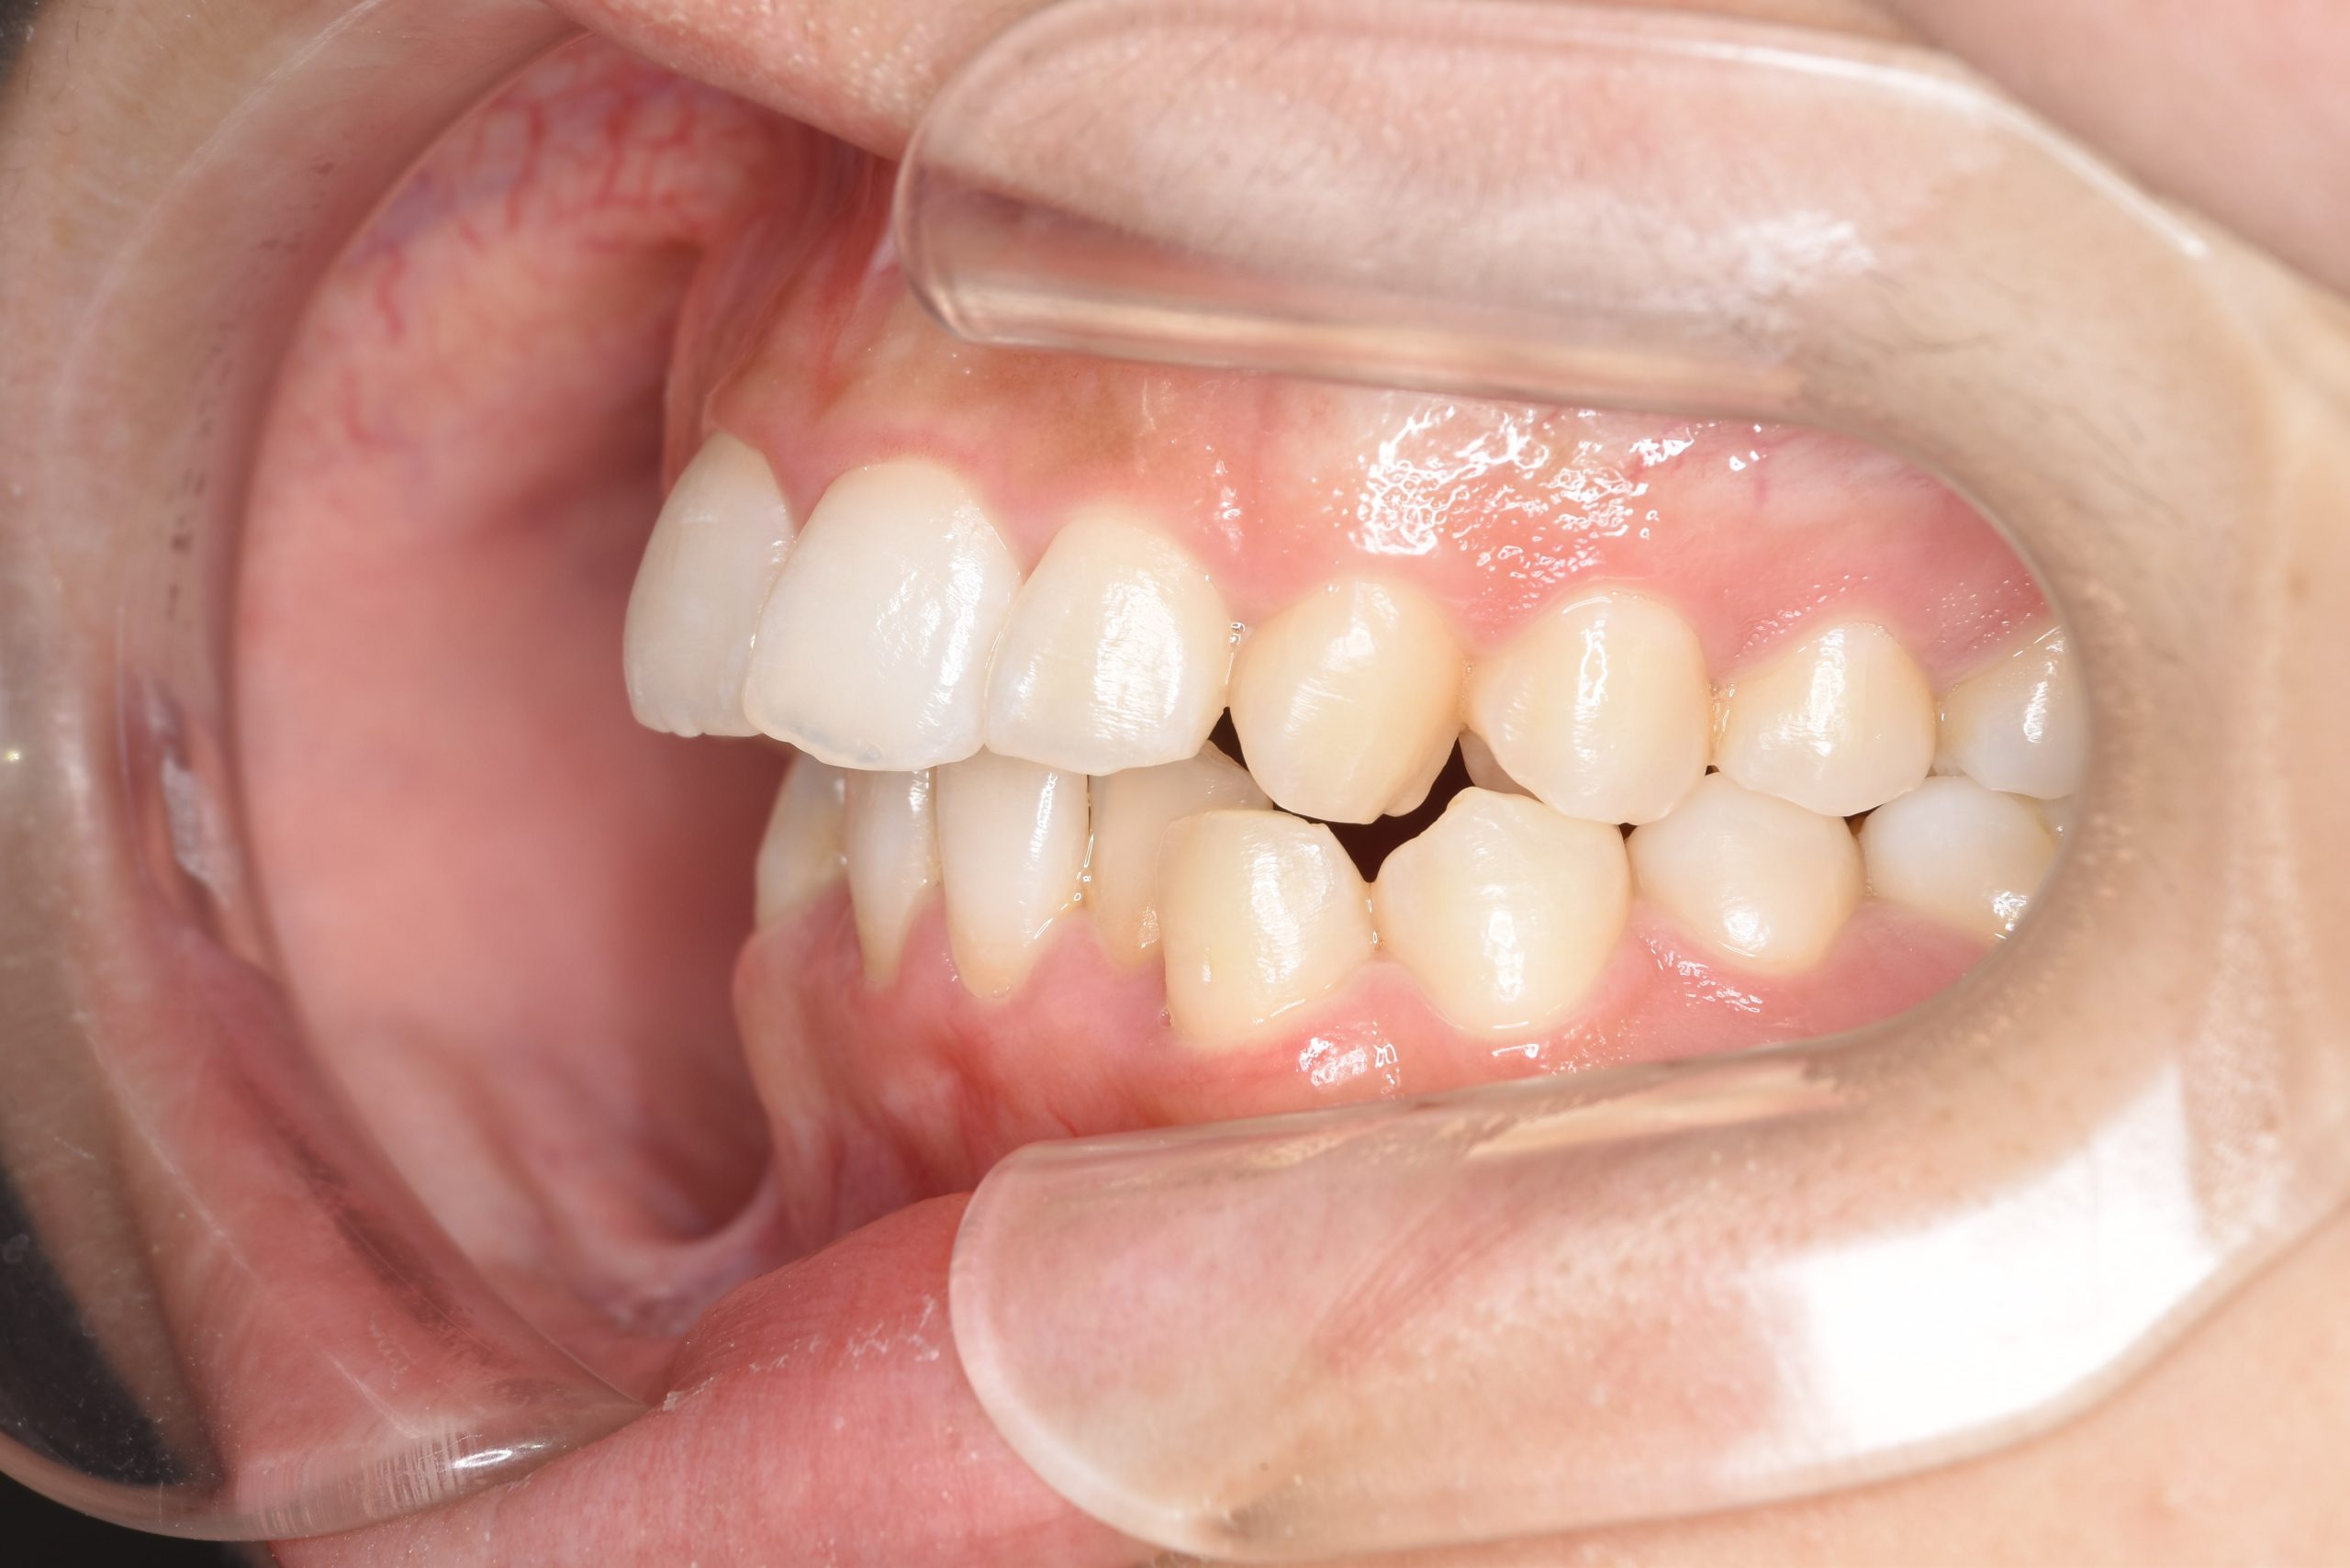

アフター

インビザライン矯正治療|症例_315

主訴 食べ物を前歯で噛み切れない|上顎の右側の歯が重なっている|下の歯がガタガタ

施術内容 MSEと下顎リンガルアーチを用いて上下顎骨を拡大した。

その後アライナー型矯正装置(インビザライン)を用いて非抜歯で歯牙を配列した。

口元の突出感、鼻閉症状、鼾は改善された。